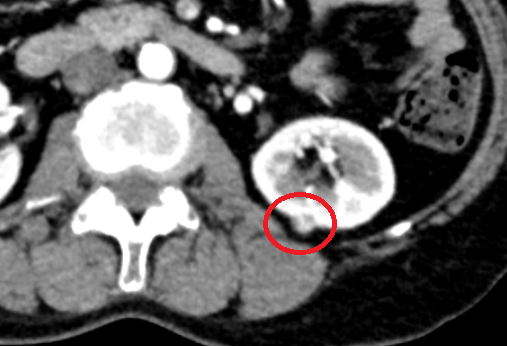

CT상에서 1.4cm크기의 조영증강이 되는 작은 병변이 왼쪽 신장에서 보였습니다. 해당 병변은 신장암의 가능성이 있는 병변이라 상급병원으로 전원을 하였습니다.

• 복부CT 횡단촬영: 신장 병변 복부CT 횡단촬영: 신장 병변